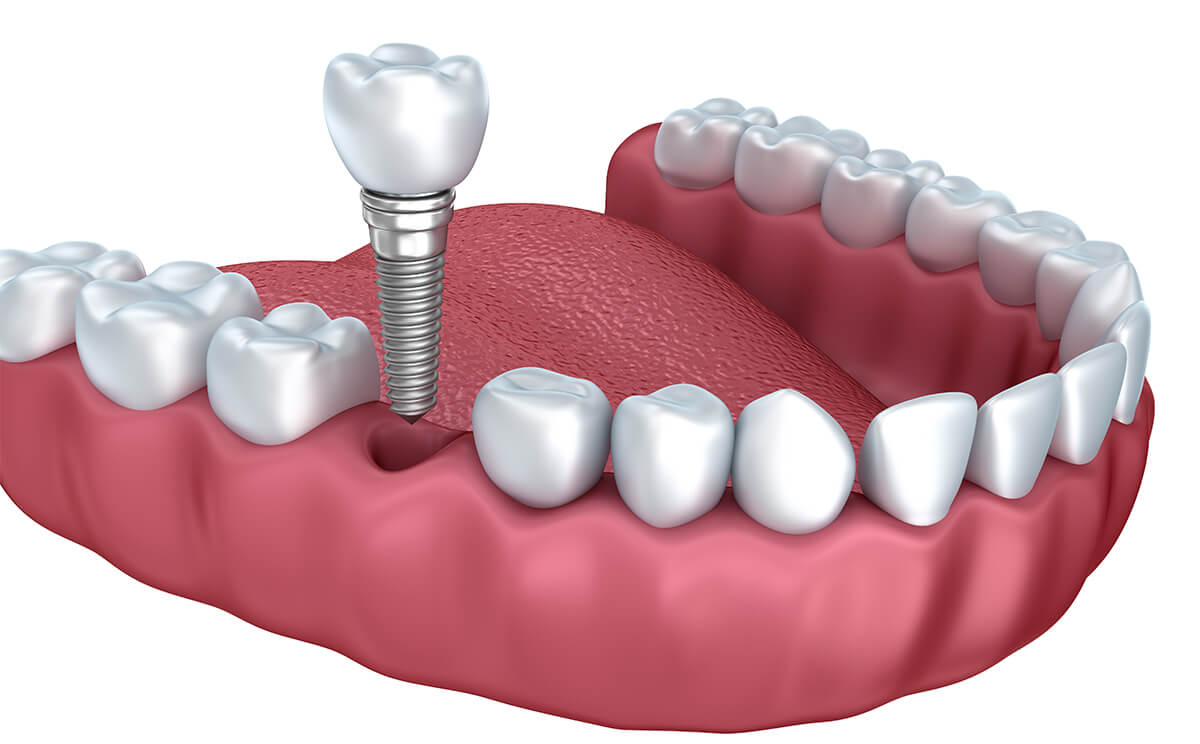

Same-day teeth implants work best when restoring an entire arch or all of your teeth using all-on-four or all-on-six implants. In traditional implant treatment, patients wait months for their implant to integrate into their bone system before receiving a supportive abutment or restoration to replace lost teeth. With teeth in a day, there’s no waiting period between implant placement and getting new teeth.

On the date of your surgery, your dental surgeon will place four or six implants strategically in your mouth to support your new teeth. These implants are placed at an angle within your jaw where your bone is thickest. Once the implants are in place, we’ll attach an arch of fully functional temporary teeth for you until the customized permanent teeth can be made. Your smile is restored in one day rather than waiting months to receive new teeth.

Once your permanent restorations are ready, we’ll schedule a follow-up visit to remove your temporary prosthetics and install your permanent replacement teeth.